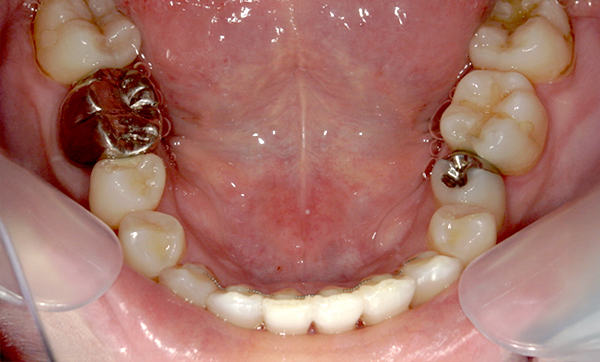

症例_009 「上下の前歯」症例

治療期間:7ヶ月金額:54万円+税20代女性捻転歯一部の反対咬合前歯のガタガタ